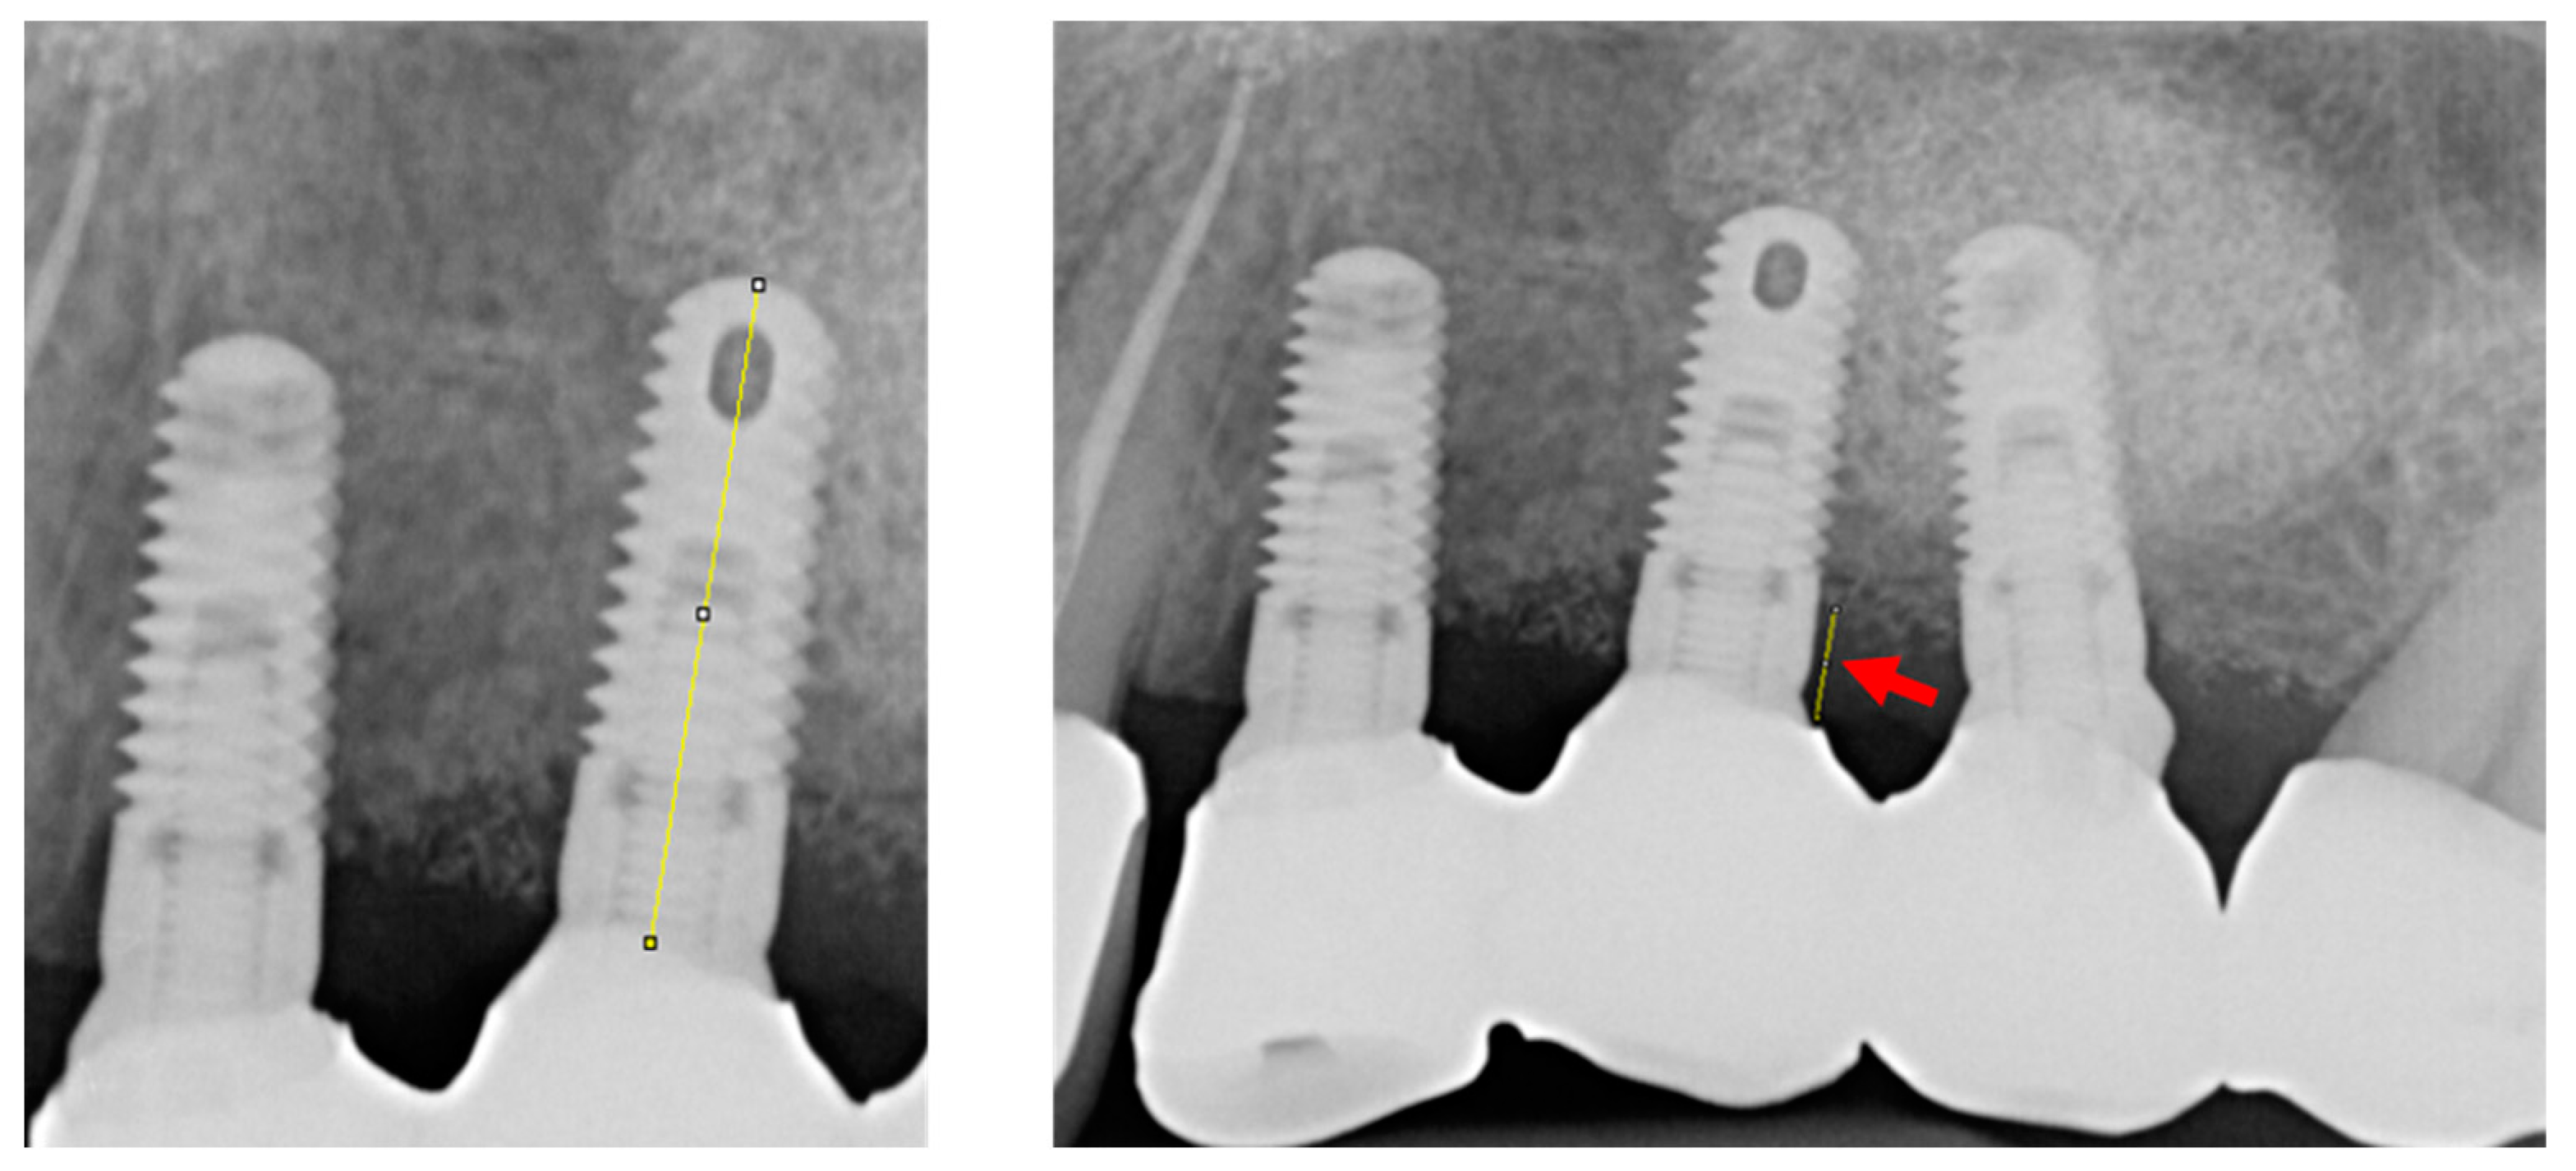

2.4. Implant Success and Peri-Implant Marginal Bone Loss